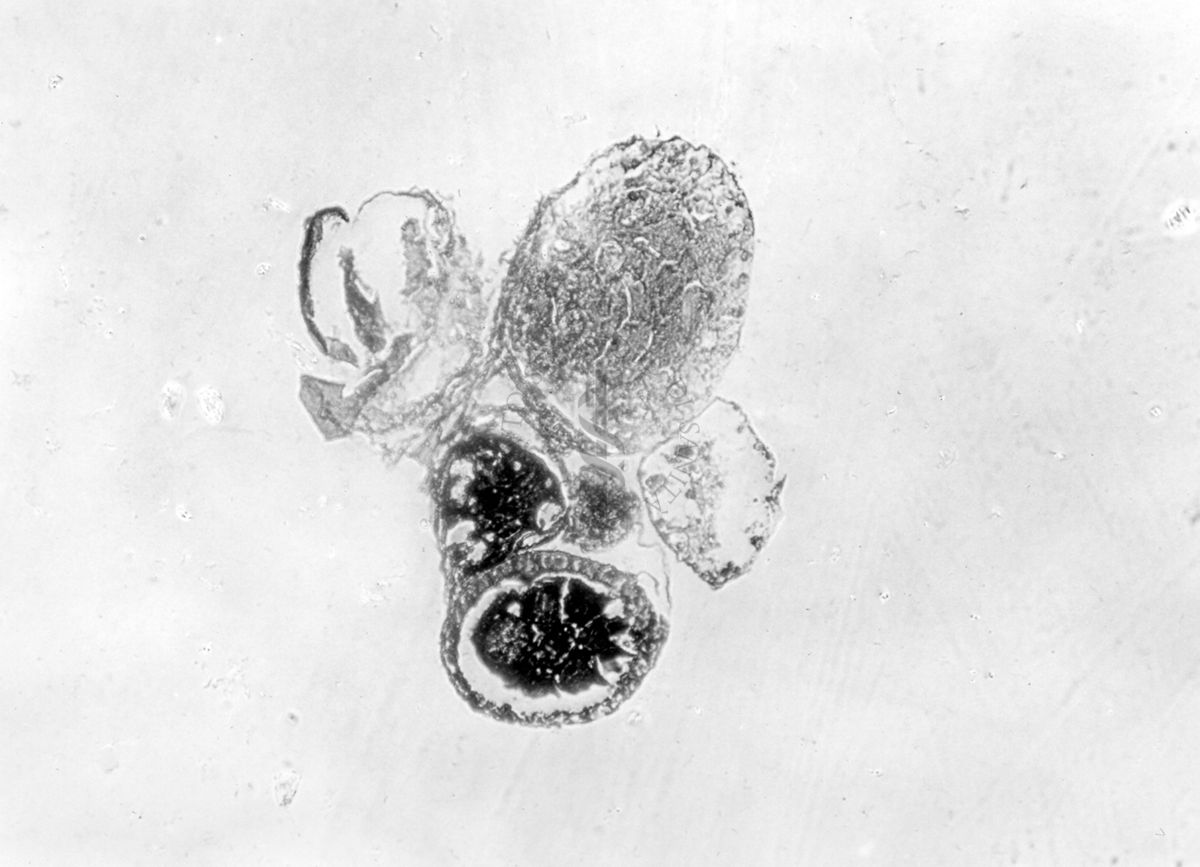

Sezione di un testicolo articolato ad un ovidutto, gonadi con epitelio esterno di sesso opposto ai prodotti sessuali, sezione di 2 gonadi di sesso opposto, immature e articolate a ovidutti

Sezione di un testicolo articolato ad un ovidutto